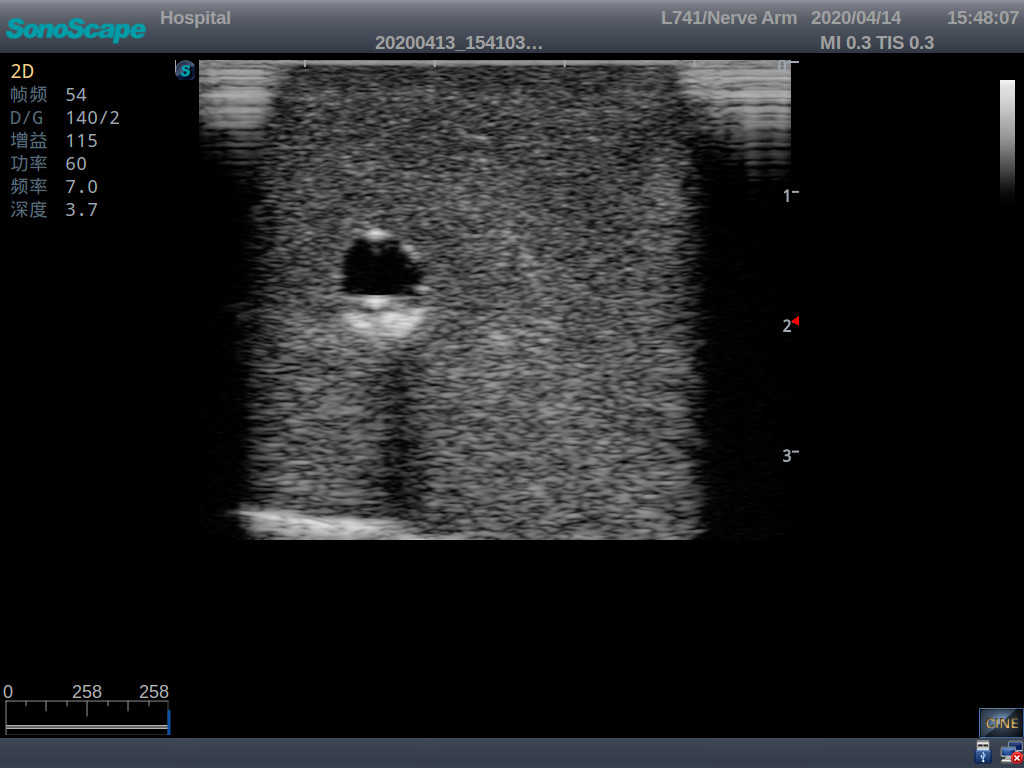

Product size(mm) 700×500×160

It is a model covering up from lobulus auriculae plane to the umbilical plane, and it has anatomical structures like clavicle, rib, sternocleidomastoid, jugular vein and basilic vein.

1)   Made of high molecular polymer ultrasound material, close to the real skin

2)   It can be used by real ultrasound machines

3)   Clear and real images of the tissues and organs (basilic vein and superior vena cava)

4)   When conducting vascular puncture, the piercing can be truly felt, and venous blood outflow can be seen